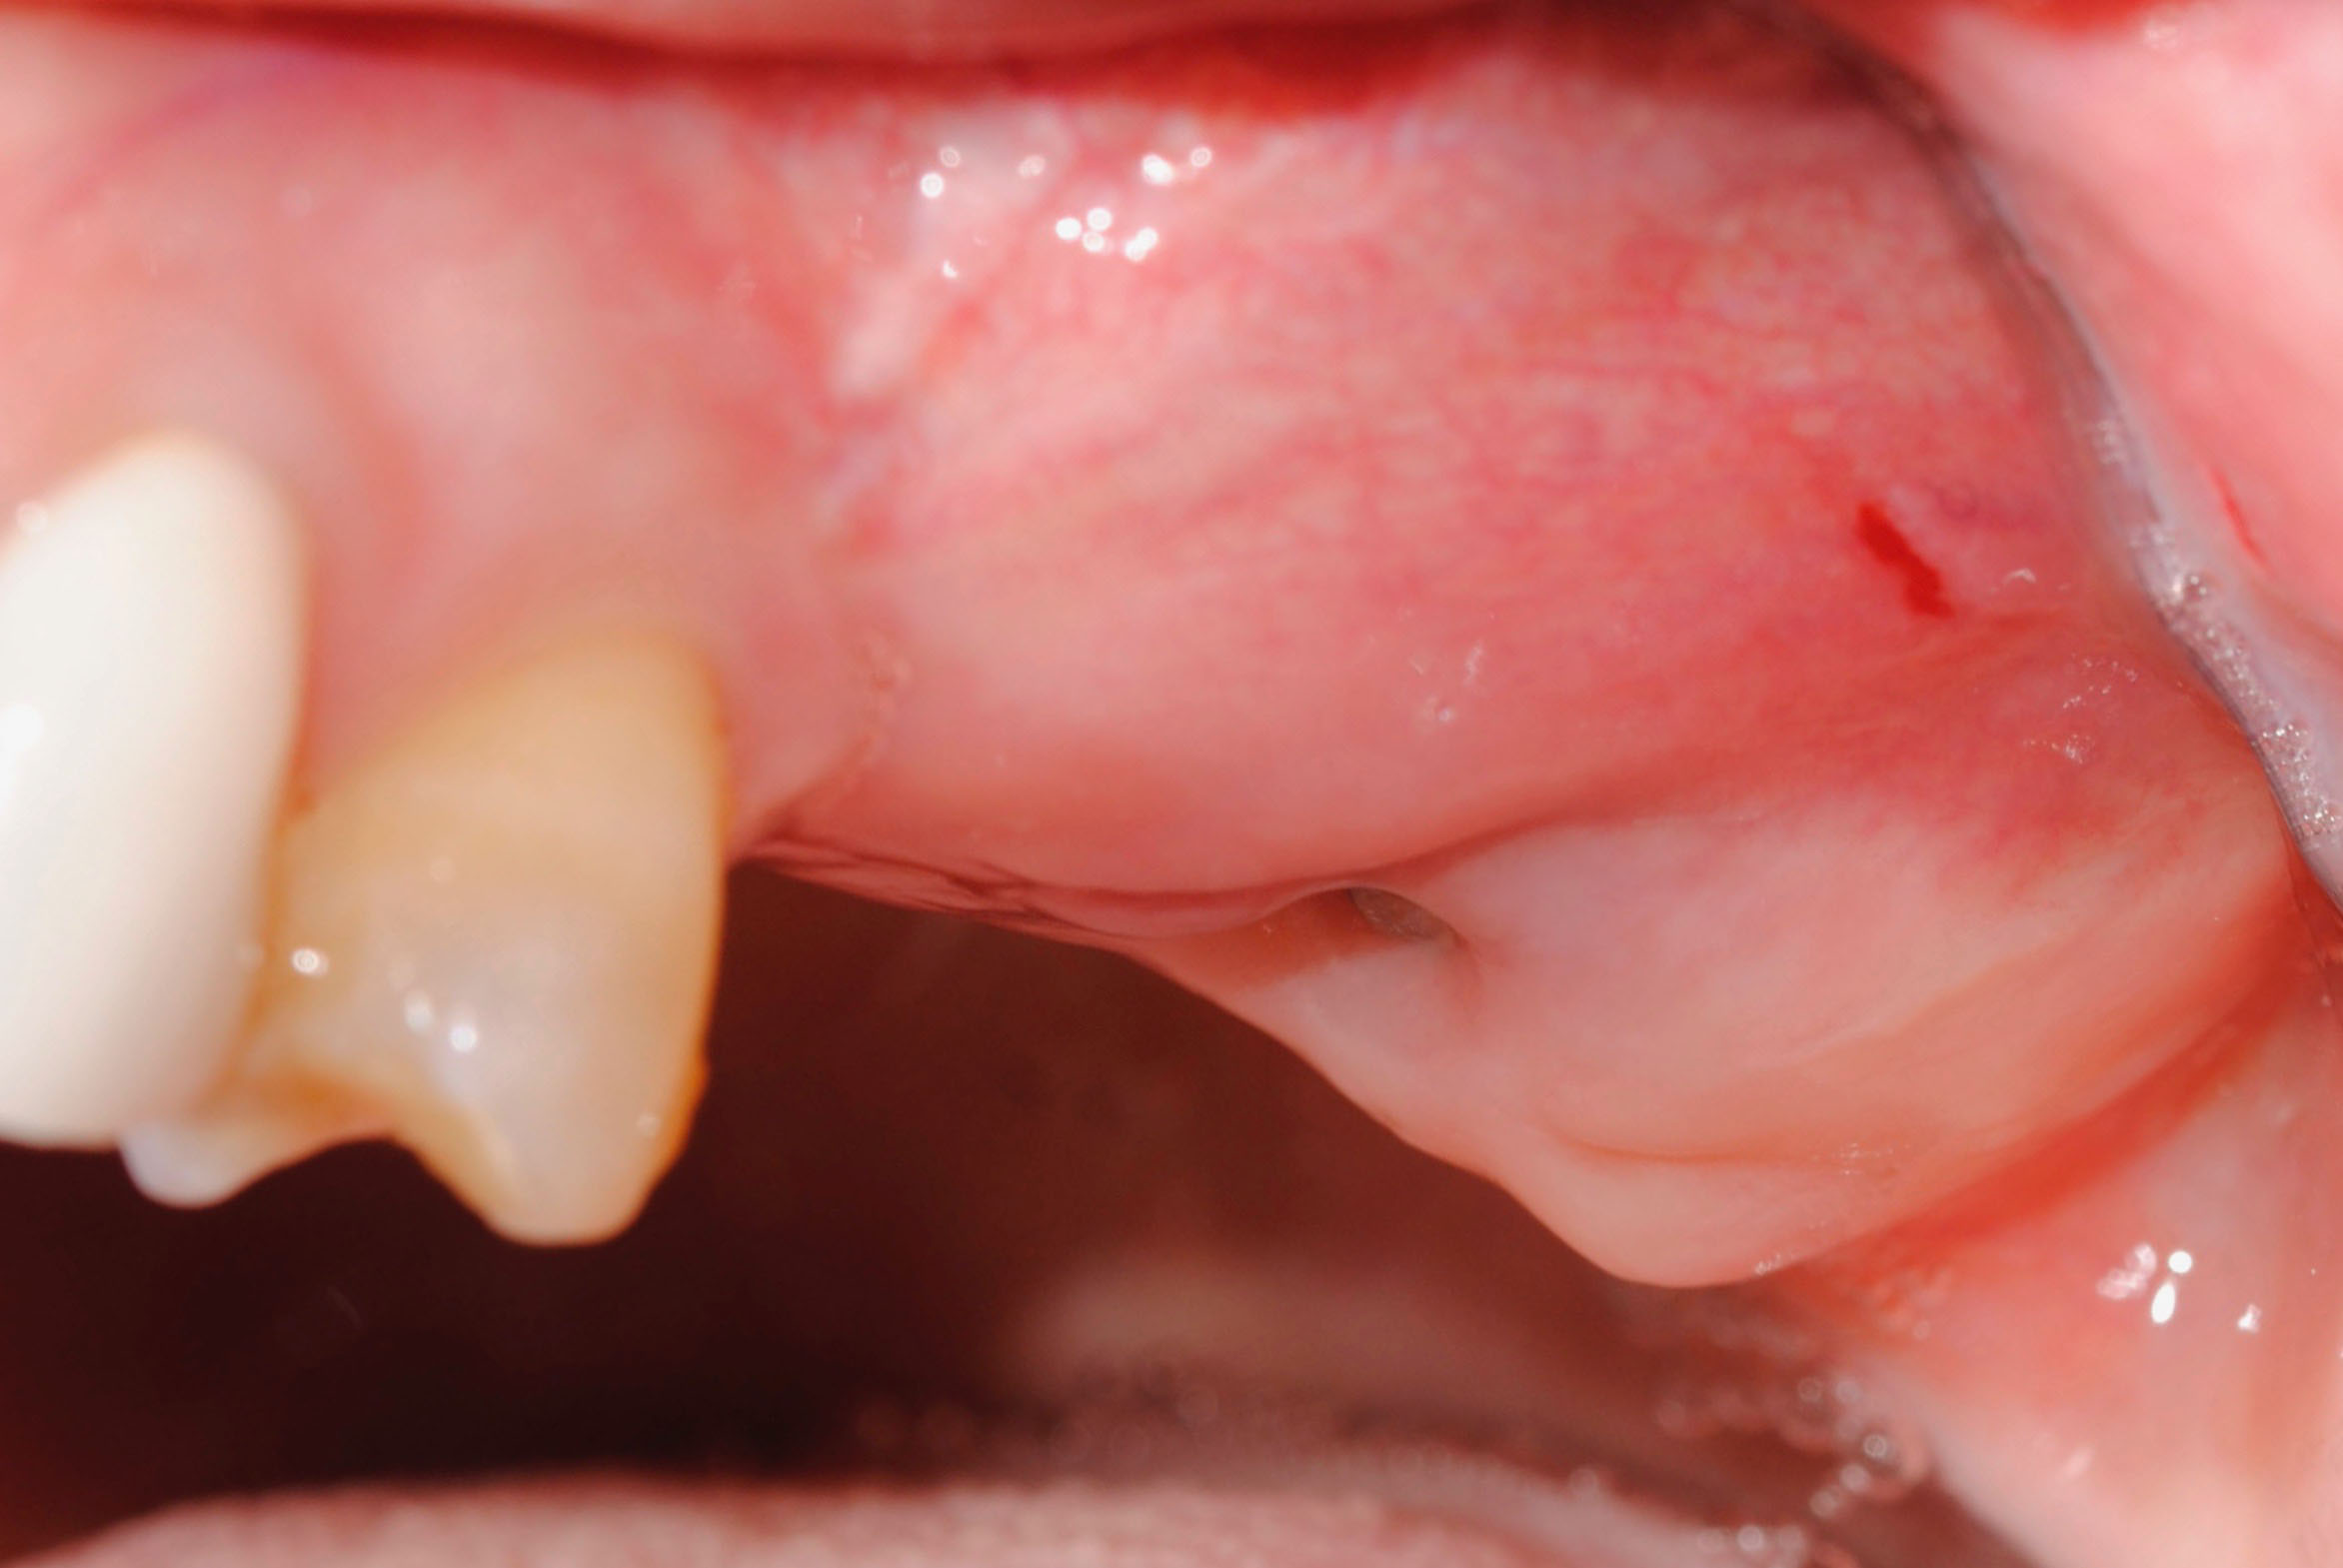

Estos son los resultados que hemos podido ver en las revisiones:

- Cuando madure el injerto, colocaremos coronas provisionales de larga duración sobre los implantes y observaremos evolución antes de hacer las coronas de cerámicas sobre implantes 26 y 27 antiguos de otra clínica con previa elevación de seno en segundo cuadrante.